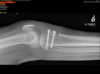

Next. I used intra-operative fluoroscopy to localize my tibial tubercle transfer. My goal was to elevate -1-2cm and medialize 1-2 cm. I measured this intra-operatively then placed two Steinman pins proximally and distally in the tibial tubercle graft through the posterior cortex. I was then able to use fluro and Measure the screw distances. The screws, in sizes of 5 so I found the appropriate screws, added a washer. The screws are self-tapping so use power then and to ensure excellent compression at the ostomy site. I then used fluoroscopy to confirm appropriate hardware localization. Tourniquet time was 65 minutes with an estimated blood loss of 20 mL.

Patient was also concerned about the remaining screws so we ordered a CT scan to assess healing. Interval callus formation so we added a bone scan